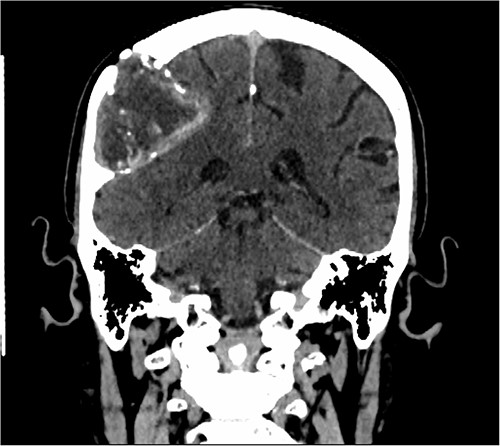

Our patient is a 76-year-old gentleman with medical history of hypertension and lumbar spondylosis. He did not have any previous history of trauma or systemic infections. He had presented to his local hospital with a 2-day history of left arm numbness. He did not report any headaches or giddiness. On clinical assessment, he did not have any neurological deficits. A CT brain and MRI brain (Figs 1–5) with contrast revealed a 53 × 53 × 41 mm partially calcified, heterogeneously enhancing conical shaped right extra-axial parietal convexity lesion. The overlying calvarial bone was remodelled and possibly eroded. There was evidence of prior haemorrhage within the lesion and scattered internal and peripheral calcification. Based on these characteristics, the possible diagnoses were that of an intraosseous meningioma, haemangioma and giant cell tumour. Patient was consented for craniotomy and excision of the tumour.

Sagittal CT scan showing the extra-axial lesion with surrounding bone remodelling and evidence of the bone erosion as well.